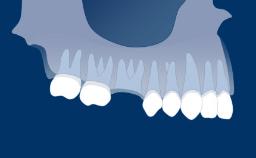

O uso de próteses dentárias implantossuportadas para substituir dentes perdidos resultou em um foco renovado nas técnicas de extração, particularmente na zona estética. A remoção do dente sem danificar o alvéolo pode facilitar a cicatrização pós-operatória, as técnicas de preservação do rebordo e a subsequente instalação do implante. Este módulo descreverá as técnicas para remover um dente condenado, com a instalação do implante em mente.

- reconhecer fatores que podem levar à extração dentária

- descrever os efeitos biológicos da perda dentária no processo dentoalveolar